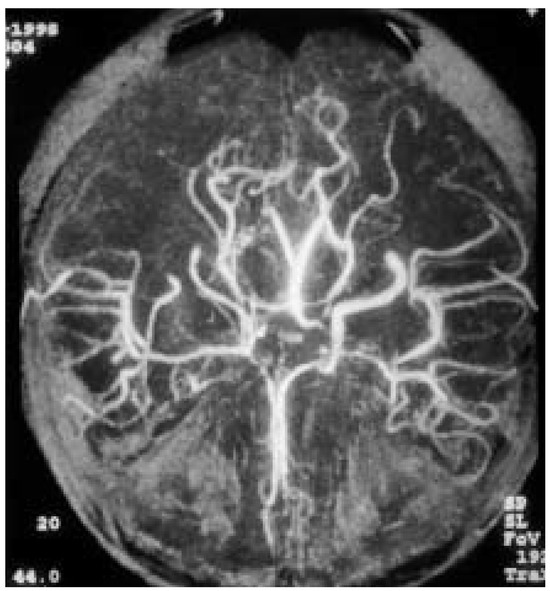

Rarely, adult moyamoya disease presents with recurrent migraine-like headaches during a long course.We report the case of a 31-year-old woman with moyamoya disease and migraine-like headaches, with a 13-year history. Physical examination showed no neurologic deficits. Magnetic resonance angiography (MRA) and digital subtraction [...] Read more.

Rarely, adult moyamoya disease presents with recurrent migraine-like headaches during a long course.We report the case of a 31-year-old woman with moyamoya disease and migraine-like headaches, with a 13-year history. Physical examination showed no neurologic deficits. Magnetic resonance angiography (MRA) and digital subtraction angiography (DSA) showed occlusion of the right internal carotid artery (ICA), severe stenosis of the left ICA, and abnormal vascular network at the base of the brain. The calcium channel blocker, nimodipine, was introduced in order to prevent further symptoms. After the introduction of nimodipine, no further headache, weakness and numbness of the left hand occurred in this patient. This suggests that migraine-like headaches may be caused by moyamoya disease and that nimodipine may have a beneficial effect on this condition. Full article